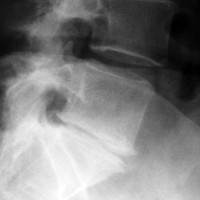

A free medical education seminar series for everyoneA FREE spine education seminar series for everyone Back pain has many faces and to many people it can be distressing, disabling or even frightening. Whether back pain comes from a strain, degenerative disc disease, a herniated disc, spinal stenosis, spondylolisthesis, a complex deformity or even a fracture, there are many options that can help you to live an active lifestyle. Additionally, osteoporosis is another disease that you may not even know you have. Learn from these dynamic experts about the various types of back problems and the latest treatments available. We will discuss the problems, the solutions and leave time for your questions to help you be active. Talk with the experts and get your concerns addressed. Spine Program